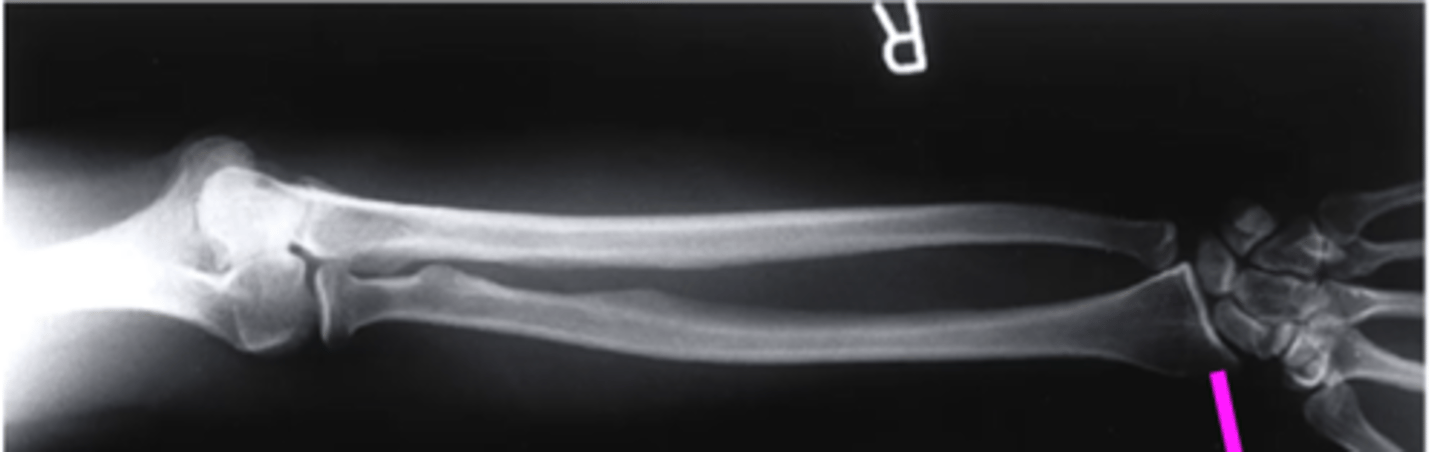

AP forearm

what view is this?

olecranon process

what does this pink line point to?

trochlea

capitulum

humeroradial joint

proximal radioulnar joint

radial tuberosity

radial styloid

distal radioulnar joint

scaphoid

lunate